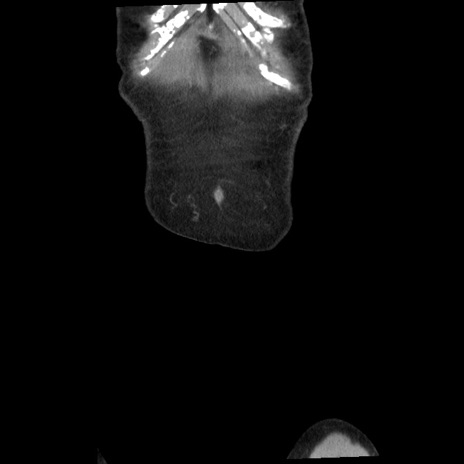

矢状断像